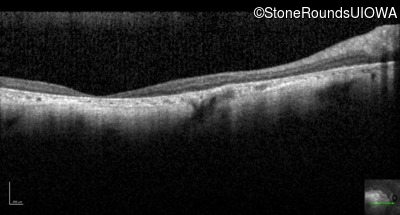

Optical Coherence Tomography - Left - Unable to Quantify

Exemplar / OCT Stack

OCT Stack